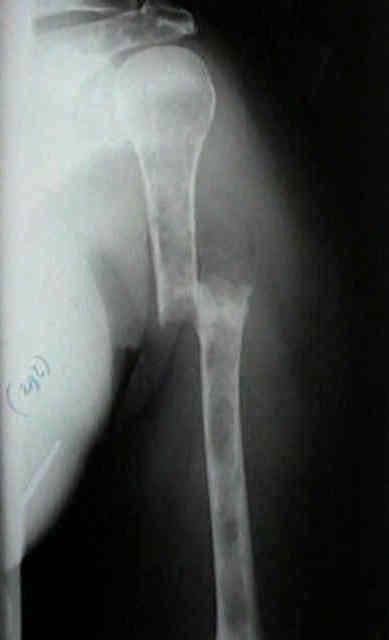

Radiographic Studies

- standard x-rays may show diffuse osteopenia

- "punched-out lesions" w/ no surrounding new-bone formation;

- over time lesions may change from diffuse osteopenia to more permeative moth-eaten destructive pattern, sometimes w/ cortical expansion;

- bone destruction occurs w/ little or no reactive bone formation unless pathologic frx is present;

Surgical Fixation

- Treatment of pathologic fracture of the humerus.